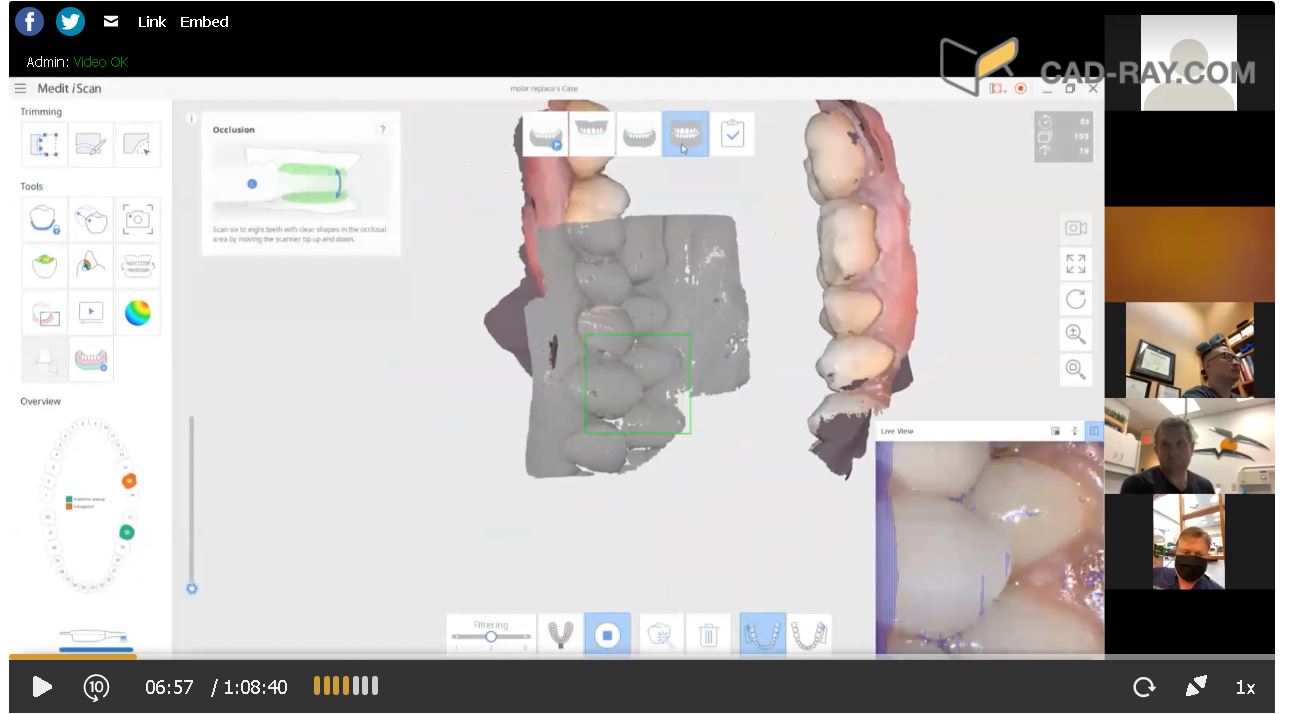

This video shows how the vertical dimension was captured with cotton rolls blocking out the tongue and the dark oro-pharynx, which usually spell trouble for an IOS